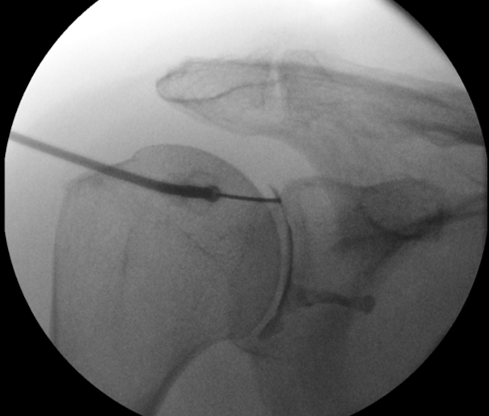

Depending on the problem the injection is targeted to the affected area. The subacromial space is easily injected. This is frequently done in an outpatient setting and rarely requires image guidance. The AC joint and the Glenohumeral joints are less reliably injected unless image guidance is used (typically x-ray or ultrasound)

When injecting into the Glenohumeral joint we use Omnipaque (Iohexol). This is an iodine based solution which shows up on x-ray allowing us to confirm we are in the correct place for injection.